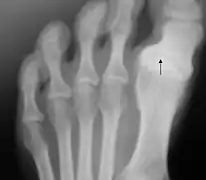

Hallux varus

L'hallux varus est une déformation de l'articulation du gros orteil.

Hallux varus congénital chez un enfant de 10 mois

Cette déformation inhabituelle peut être congénitale ou acquise à la suite d'un traumatisme. Prise tôt, une réduction manuelle est possible, par le port de semelles par exemple. Sinon, selon l'avancement, le degré de déformation et le niveau d'arthrose, on pourra déplacer le tendon ou faire une arthrodèse.

Elle peut aussi survenir de façon exceptionnelle et imprévisible après une opération de l'hallux valgus dans laquelle la correction de l'alignement du gros orteil a été exagérée.